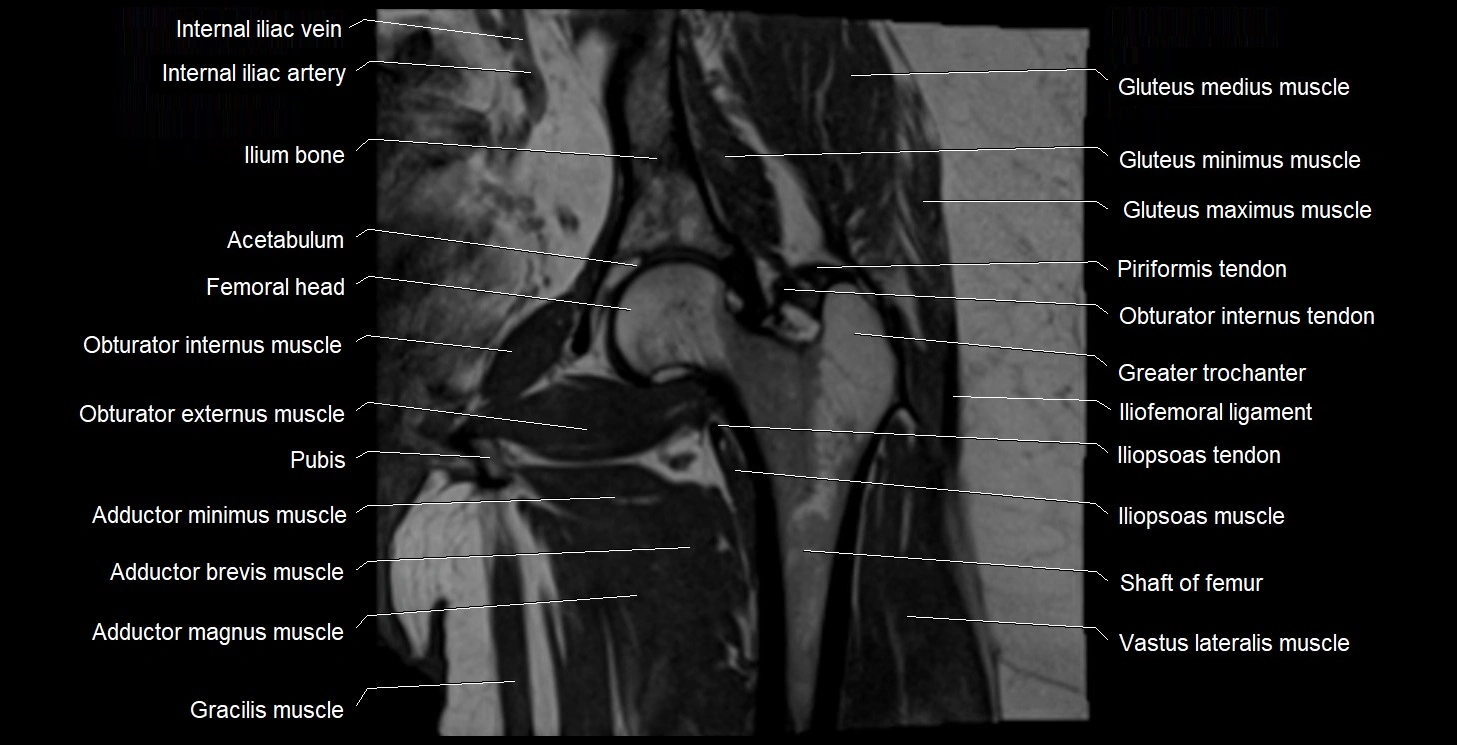

- Acetabulum

- Adductor brevis muscle

- Adductor magnus muscle

- Adductor minimus muscle

- Gracilis muscle

- Greater trochanter

- Head of femur

- Iliofemoral ligament

- Iliopsoas muscle

- Iliopsoas tendon

- Ilium bone

- Obturator externus muscle

- Obturator internus muscle

- Obturator internus tendon

- Vastus lateralis muscle